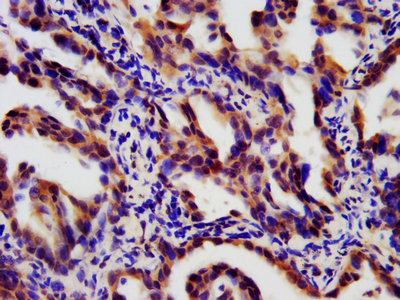

LTBR 屬于Ⅰ型單跨膜蛋白 [1],是腫瘤壞死因子受體(TNFR)家族的成員 [2]。完全糖基化的LTBR分子量為61kDa,去除糖基化修飾后,理論分子量降至47kDa [3]。其胞質(zhì)結(jié)構(gòu)域由 175 個氨基酸組成,靠近細(xì)胞膜區(qū)域富含脯氨酸殘基,這一結(jié)構(gòu)特點使其能像其他TNFR家族蛋白一樣,直接與腫瘤壞死因子受體相關(guān)因子(TRAF)蛋白相互作用,在細(xì)胞信號傳導(dǎo)中發(fā)揮關(guān)鍵作用 [4]。LTBR蛋白結(jié)構(gòu)包括胞外區(qū)、跨膜區(qū)和胞內(nèi)區(qū)(圖 1)。胞外區(qū)負(fù)責(zé)與配體結(jié)合,識別特定信號分子;胞內(nèi)區(qū)則通過與TRAF蛋白相互作用,啟動細(xì)胞內(nèi)信號傳導(dǎo)通路,進(jìn)而調(diào)控細(xì)胞的生物學(xué)行為 [5]。

圖1:LTBR蛋白的結(jié)構(gòu)組成

圖源:https://www.uniprot.org/uniprotkb/P36941/entry